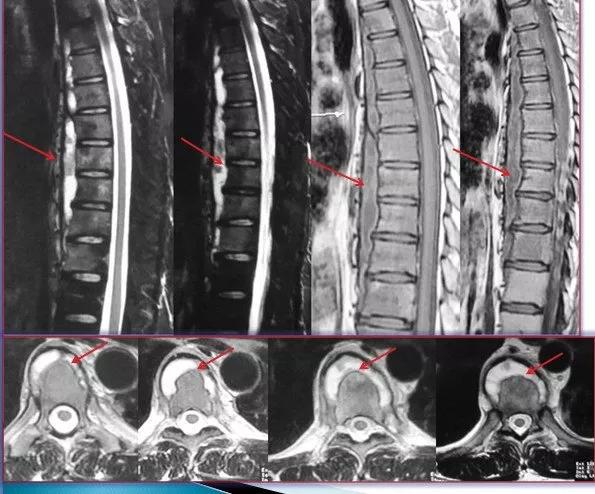

3、这是一个年轻男性患者,也是因轻微背痛就诊。影像检查发现胸椎结核。从核磁看(红色箭头示)胸椎多节段椎前广泛脓肿,只有两个椎体和椎间隙有明显炎性病变或破坏。

患者是年轻人,轻微背痛,活动甚至体育锻炼都不受影响,可以采取保守治疗。制定抗结核治疗方案后,定期随诊复查。抗结核治疗六个月后,脓肿没有吸收,还较以前增大(红色箭头示),但患者活动锻炼没有任何影响,椎体及间盘破坏也无加重。继续保守治疗,调整抗结核药物组合方案,并辅以中药治疗。

抗结核治疗九个月后,脓肿明显吸收(红色箭头示)。